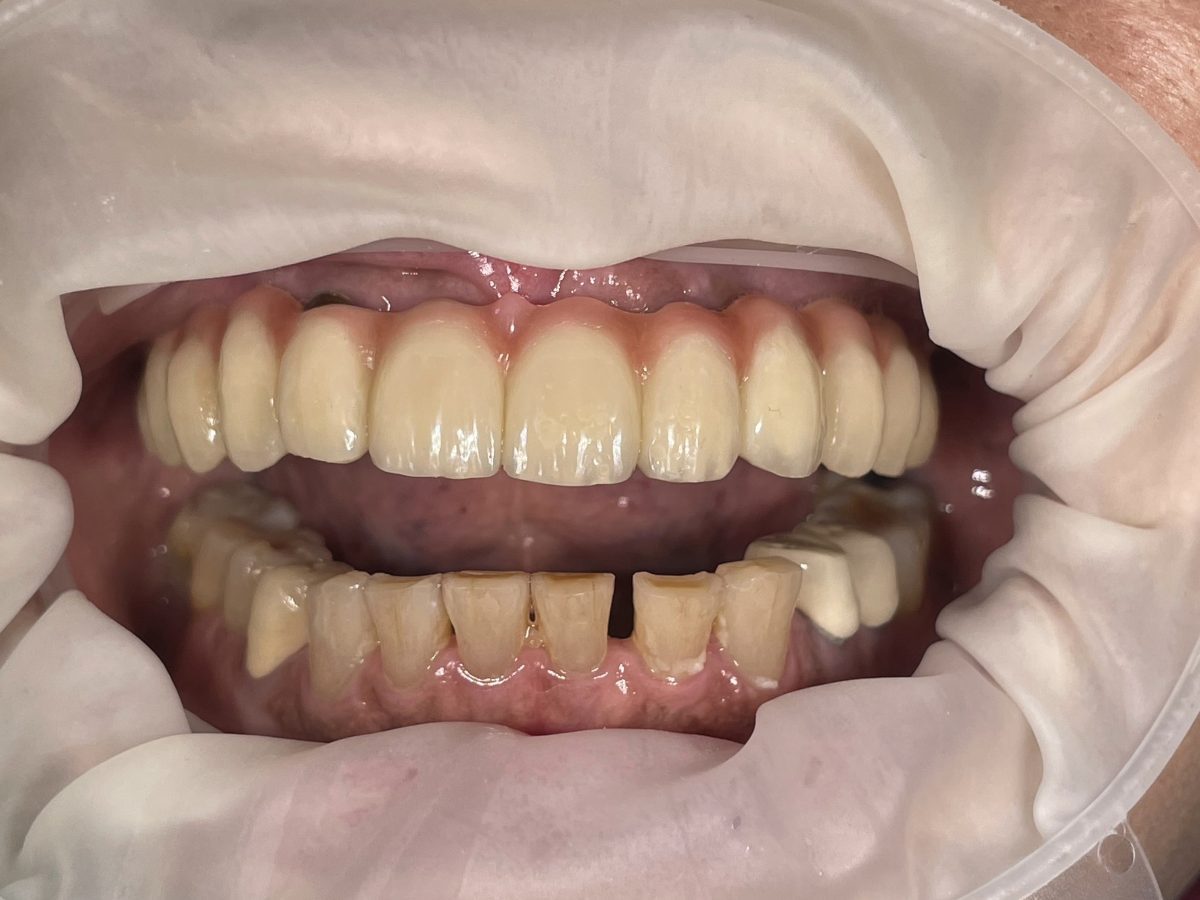

All-on-X dental implants are a full-arch restoration solution designed for patients with multiple missing, damaged, or failing teeth. The treatment uses four, five, or six dental implants to support a fixed full-arch prosthesis, restoring both function and aesthetics.

Full mouth rehabilitation is a comprehensive dental treatment designed to restore both function and aesthetics for patients with severely worn, damaged, missing, or failing teeth.

Treatment may include a combination of:

* crowns

* veneers

* dental implants

* bridges

* gum treatment

* bite rehabilitation

Each treatment plan is customized based on the patient’s oral condition and long-term goals.